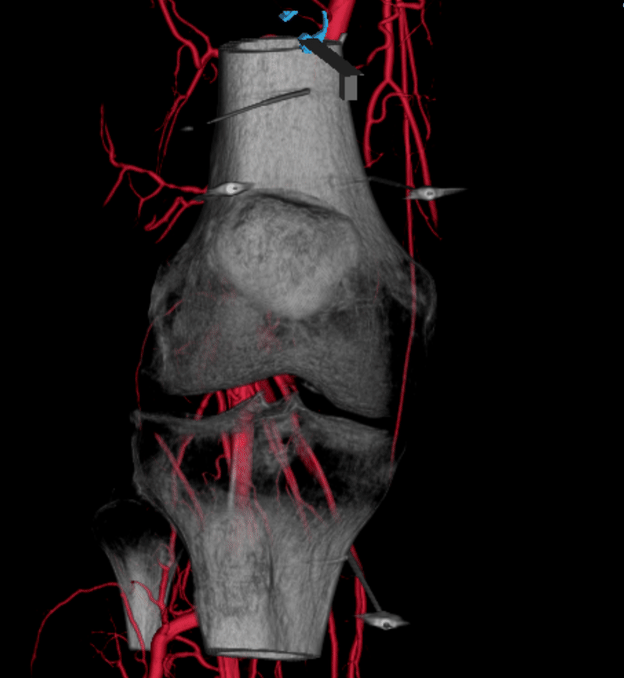

Sometimes TAME can be combined with genicular nerve block or ablation, either with RFA or cryoablation. This complete genicular neurovascular treatment (GNT) is a specialty of our team at Spectrum IR.

Intraprocedural 3D Reconstruction from a case of genicular neurovascular treatment combining genicular nerve RFA with genicular artery embolisation.